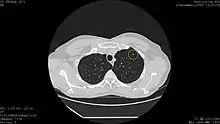

Calcified lung nodule seen on Low Dose Chest CT (circled)

Calcified lung nodule seen on Standard Dose Chest CT (circled)